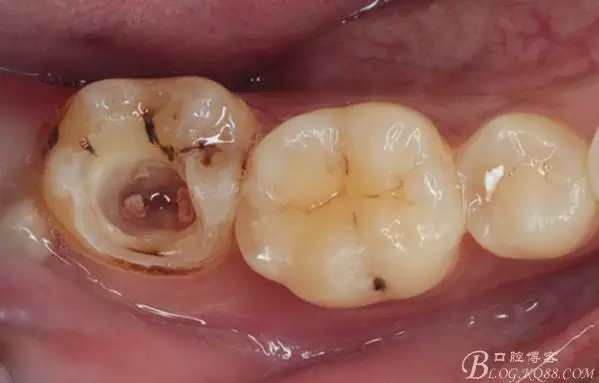

口腔檢查:37頰頜面齲洞,叩(+),探(+),冷熱測試與對照牙對比為敏感。17 27 47 均有不同程度齲壞,無明顯陽性體征。18 28 38 48 呈不同程度傾斜,38 48牙冠部分萌出。全口牙齒排列不整齊,口腔衛(wèi)生較差,牙石(++),部分牙齦發(fā)紅。X線檢查示37牙冠低密度影像累及牙髓,牙周間隙略增寬。

去除暫封物,拍照,比色。